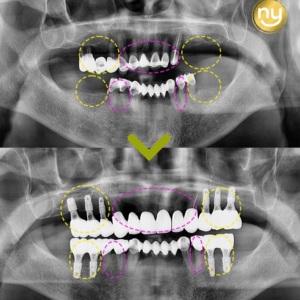

울산삼산치과 전악임플란트를 고민중이라면 안녕하세요. 울산삼산치과 뉴욕연합치과입니다. 유치는 탈락하고 난 후 영구치가 자라지만 영구치는 손상되거나 탈락 시 새로운 치아가 자라거나 손상된 부분이 회복되지 않기 때문에 조기에 예방과 관리를 하여 치아를…